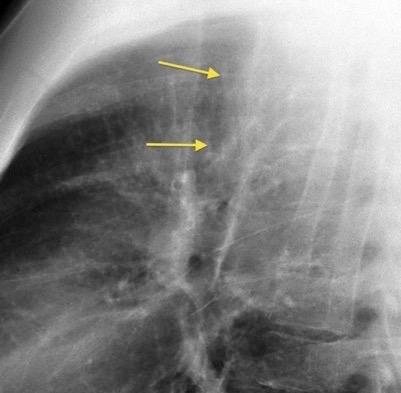

Líneas paraespinales formando un “paréntesis” por encima del diafragma. El signo señala el origen “intratorácico” de la lesión.

Conrad A et al. Pott’s disease associated with large and multiple abscesses in a 30-year-old migrant from Chad. BMJ Case Rep 2018

(lesiones toracoabdominales) La divergencia de las líneas paraespinales apunta a lesión toracoabdominal, que desde el tórax desciende y penetra en el abdomen.

Signo del “iceberg” positivo en Tb vertebral

Afectación por vía hematógena. Región dorsolumbar más frecuente. Afectación inicial: irregularidad de los platillos vertebrales, disminución del disco intervertebral con esclerosis ósea adyacente. Kim. Radiographics.2001